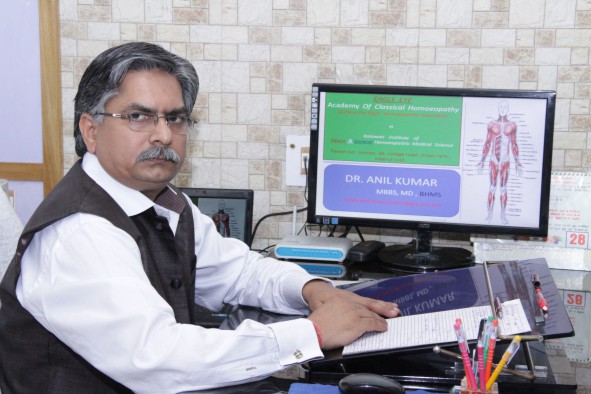

Orthopaedic

Orthopedics is a medical specialty that focuses on the diagnosis, correction, prevention, and treatment of patients with skeletal deformities - disorders of the bones, joints, muscles, ligaments, tendons, nerves and skin. These elements make up the musculoskeletal system.

Your body's musculoskeletal system is a complex system of bones, joints, ligaments, tendons, muscles and nerves and allows you to move, work and be active. Once devoted to the care of children with spine and limb deformities, orthopedics now cares for patients of all ages, from newborns with clubfeet, to young athletes requiring arthroscopic surgery, to older people with arthritis.